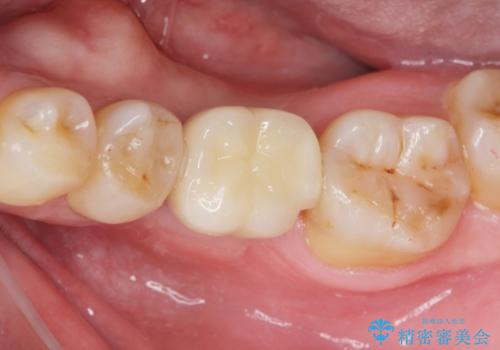

- 44万円(インプラント・チタンカスタムアバットメント・ジルコニアクラウン・仮歯)費用は治療当時の料金となります

インプラントを適切な位置に埋入することで、清掃性が高くしっかりと咬合力に耐えられるようなインプラント治療を行うことができます。